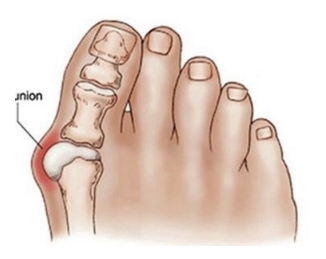

우리가 흔히 알고 있는 무지외반증 때문입니다. 사전적 의미는 엄지발가락이 안쪽으로 튀어나오는 변형이 생겼다는 말입니다. 하지만 실제로 따지고 보면 발가락과 발등을 연결하는 중족골이라는 뼈가 안쪽으로 벌어지면서 회전 변형이 같이 일어나는 질환입니다. 처음에는 증상이 없다가도 점차 진행하게 되면 발가락 안쪽이 점차 튀어나와 일반적인 신발을 신기가 불편한 증상이 생깁니다.

보행 시 첫번째 중족골이 힘을 잘 받쳐줘야 하는데 무지외반이 진행되면 다른 발가락의 중족골이 힘을 받으며 발바닥 쪽의 통증이 생기는 전이성 중족골통이 발생하기도합니다. 또한 심한 변형이 지속되면 발가락을 움직여주는 힘줄이 제 역할을 하지 못해 걷기 불편하기도 하며, 엄지발가락이 두번째 발가락을 밀면서 두번째 발가락까지 점차 변형이 진행되고 엄지발가락이 검지발가락에 올라타는 변형이 발생하기도합니다.